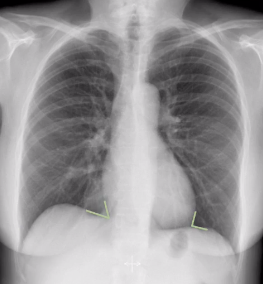

whats wrong here?

blunted cardiophrenic and costophrenic angles